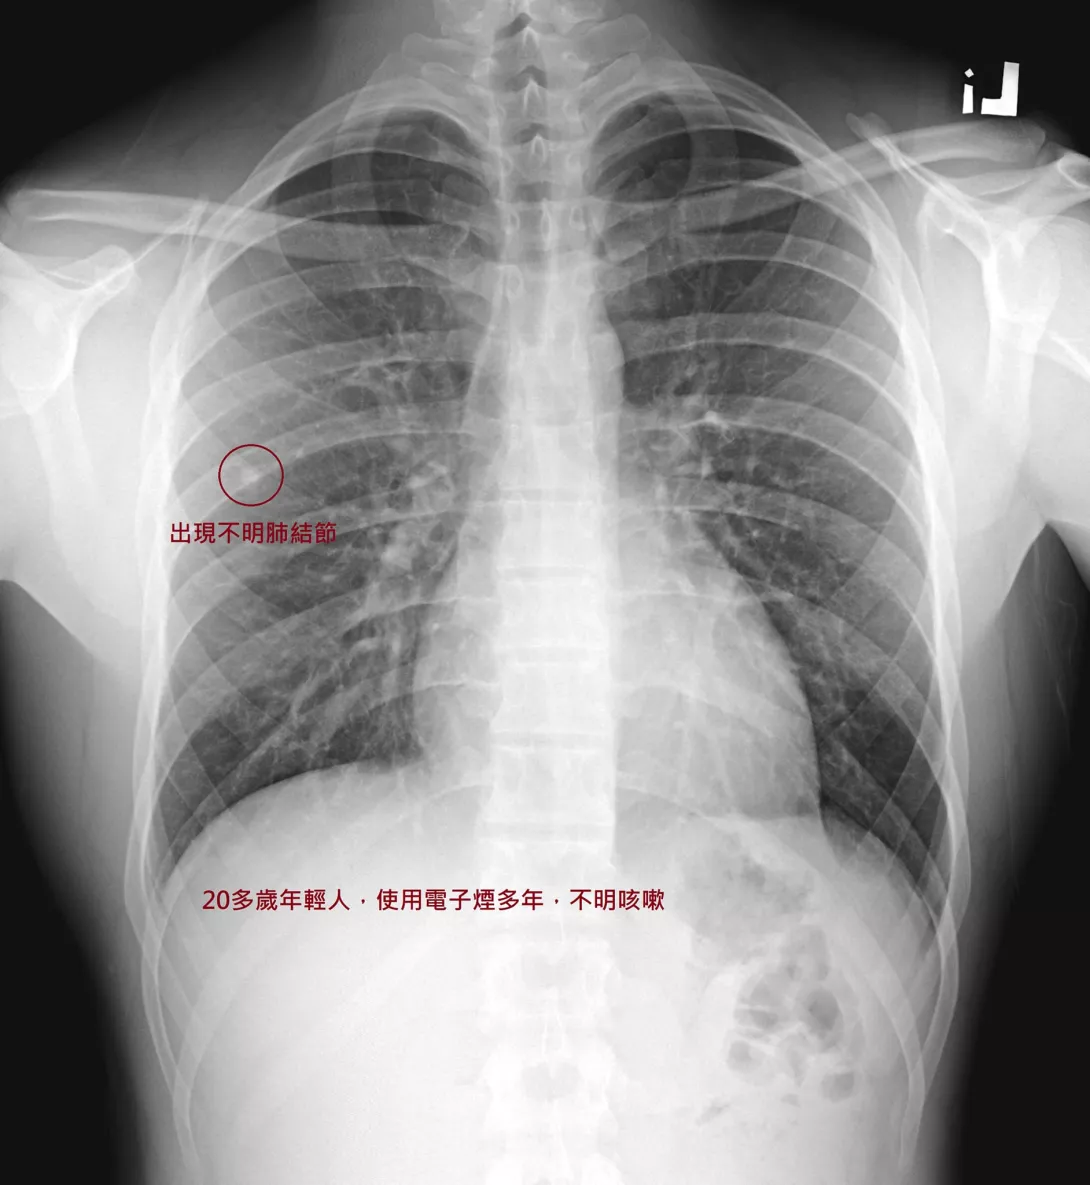

一名20幾歲男子跟著朋友學抽電子煙4、5年,且有不明原因咳嗽,日前因工作健檢,X光發現1顆近一公分大的肺結節,趕緊轉到胸腔科門診處理,並對使用電子煙感到十分後悔。

台北市立聯合陽明醫院胸腔醫師蘇一峰醫師表示,該名年輕男性患者的肺結節要後續追蹤,如果長大需考慮開刀切除。

照片

圖片來源:翻攝蘇一峰醫師臉書